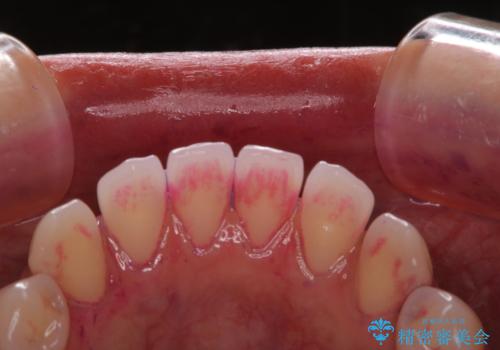

一見きれいに見える歯でも、染め出し(歯垢染色液)を使うとこのように歯と歯茎の境目や、歯と歯の間などに磨き残しがあることがわかります。歯磨きには、いつも気をつけているから磨き残しはナシと思っていても、実際完璧に磨ききることはなかなか難しいです。歯科医院にて、専門の機械で定期的なPMTCを行うことが大切です。